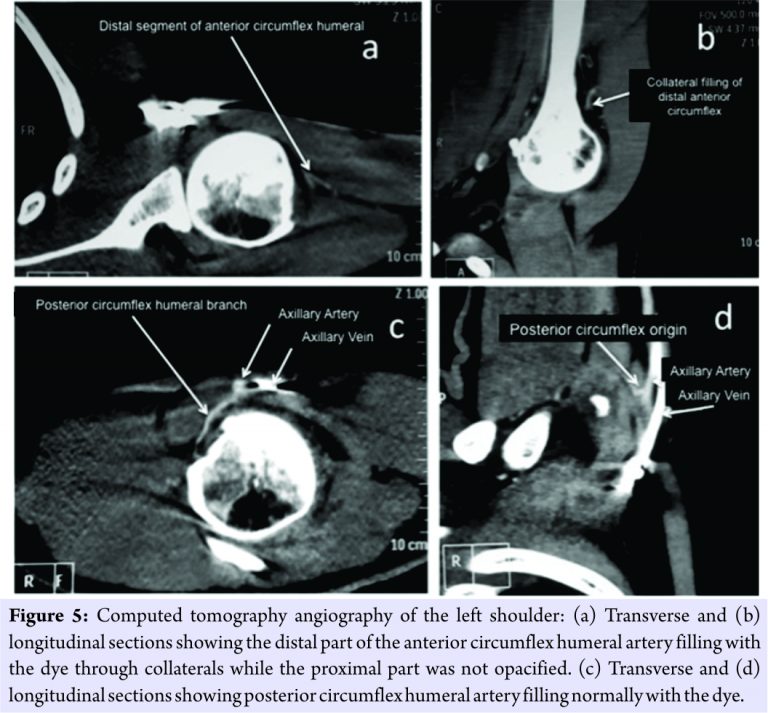

It showed attenuation of the some of the branches of anterior circumflex humeral artery, but all the vessels around the humeral neck were patent, but their course was not clearly defined. To enable a better visualization of the arteries around the neck of the humerus and to localize the site of obstruction of the artery, if any, a computerized tomography angiography of the left shoulder was performed at 2 years (Fig. 5a, b, c, and d). This study reported that the origin and proximal part of the anterior circumflex humeral artery was not opacified while the distal part of the artery was seen filling with the dye through the collaterals. The posterior circumflex humeral artery was normal. On clinical examination, the patient was able to perform 170° shoulder abduction, with a normal scapulothoracic rhythm. The power of internal rotation of the shoulder was 4/5 as per the Medical Research Council grading on the left side, and the power of the rest of the shoulder movements such as external rotation, abduction, forward flexion, and extension was 5/5. The patient was advised biceps tenodesis with subscapularis repair. However, the patient was not willing for the same.